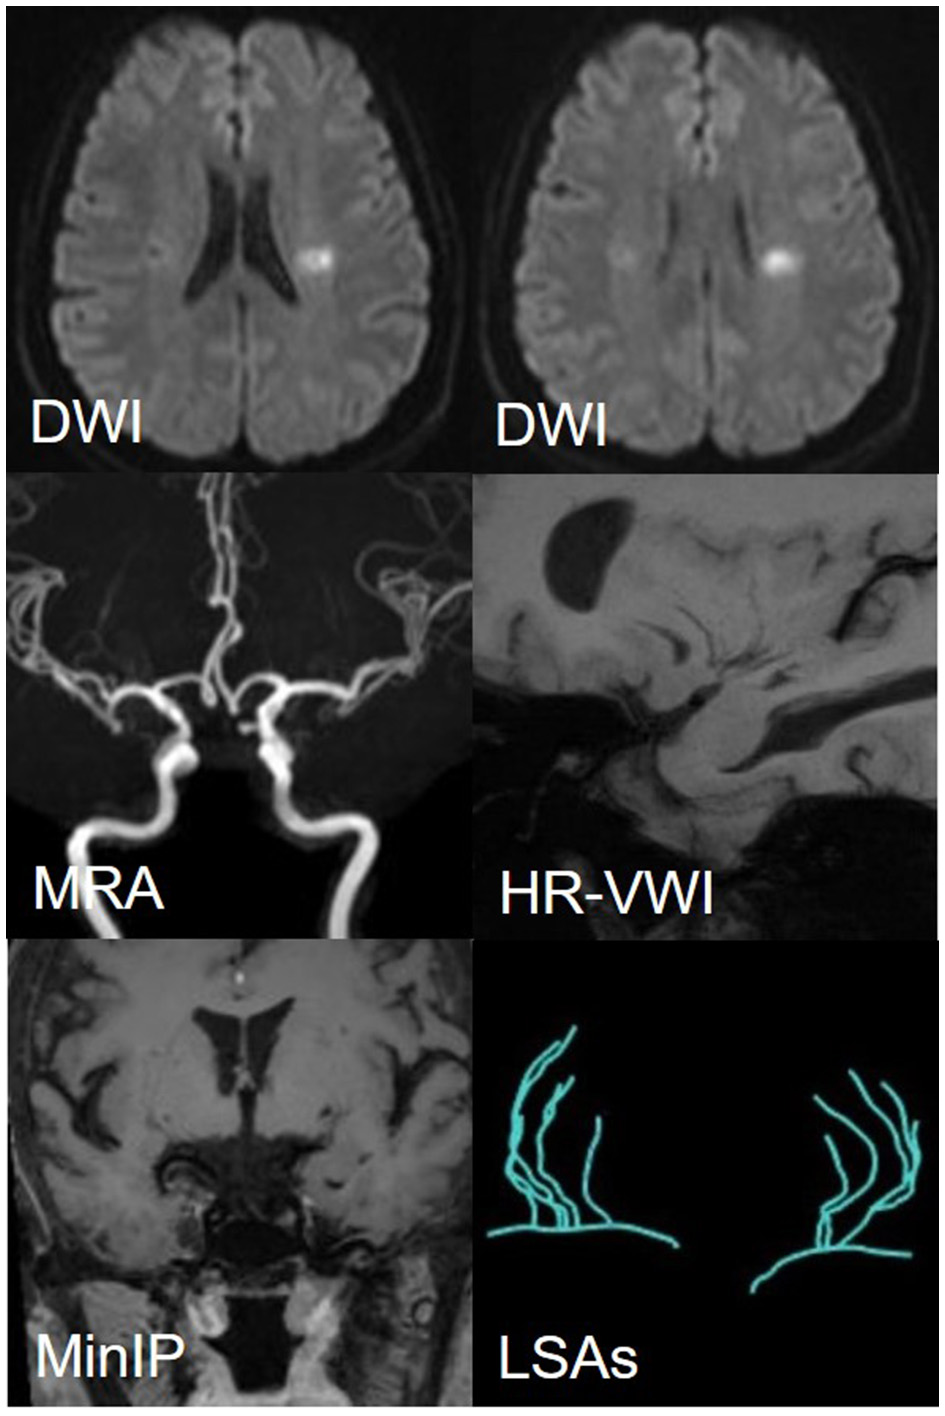

Among 110 patients, 18 were excluded, including nine due to cardiogenic embolism, one due to arteritis, four due to MCA-M1 stenosis rate >50%, and four due to poor image quality. Ninety-two patients remained. Of these, 45 were allocated to the LSI group and 47 to the SSI group. In the LSI group, 30 patients were allocated to the LAA group. In the SSI group, 28 were allocated to the SUD group and 19 to the SAD group. Ultimately, 77 patients were enrolled, and three representative cases from each group are shown in Figures 5, 6. As shown in Table 2, there were no statistical differences in risk factors or laboratory tests between the three groups (P > 0.05).

Figure 5

(A) A representative case of the LAA group: a 35-year-male. DWI shows an isolated subcortical cerebral infarction located in the LSAs territory, and the maximum axial diameter is 24 mm. MRA shows no obvious stenosis of the MCA-M1 on either side. HR-VWI shows the plaque located on the superior side of the MCA-M1. MinIP and the Sim Vascular show the LSAs' vascular skeleton. (B) A representative case of the SUD group: a 55-year-male. DWI shows an isolated subcortical cerebral infarction located in the LSAs territory and the maximum axial diameter is 12 mm. MRA shows no obvious stenosis of the MCA on either side. HR-VWI shows the plaque located on the superior side of the MCA-M1. MinIP and the Sim Vascular show the LSAs' vascular skeleton.

Figure 6

A representative case of the SAD group: a 56-year-female. DWI shows an isolated subcortical cerebral infarction located in the LSAs territory, and the maximum axial diameter is 11 mm. MRA shows no obvious stenosis of the MCA on either side. HR-VWI shows no plaques located on the MCA-M1. MinIP and the Sim Vascular show the LSAs' vascular skeleton.